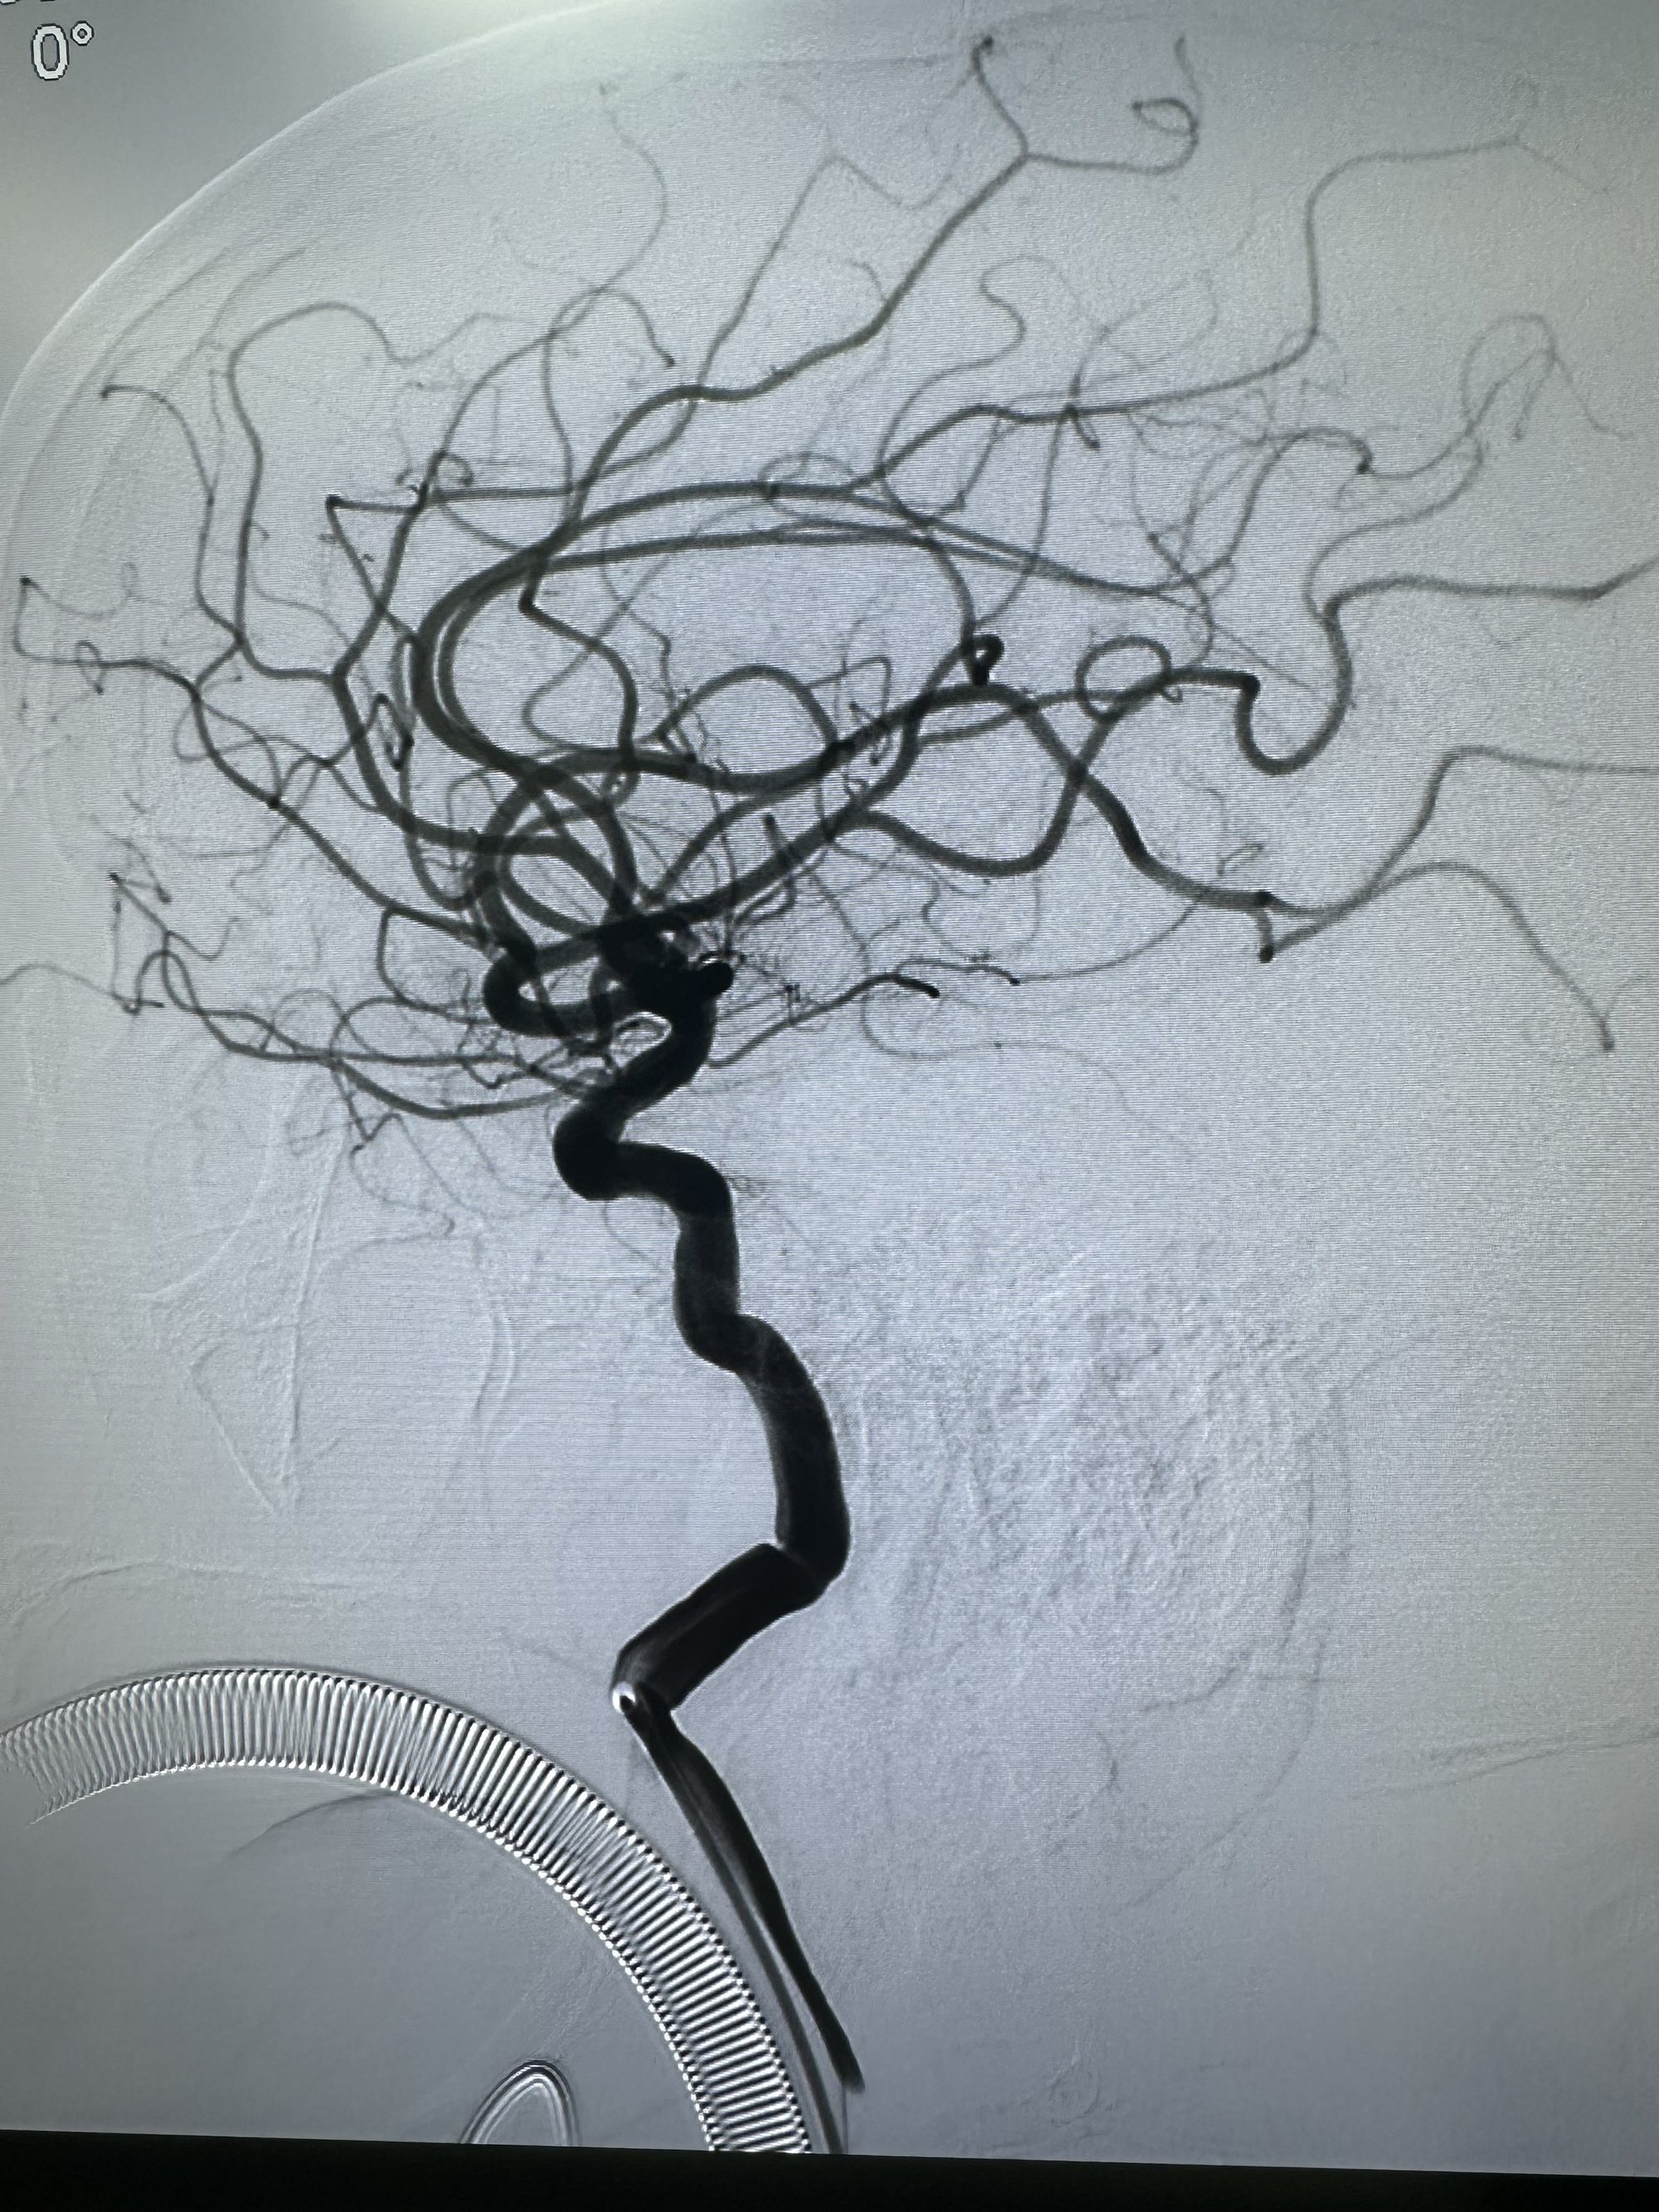

右侧颈内动脉造影